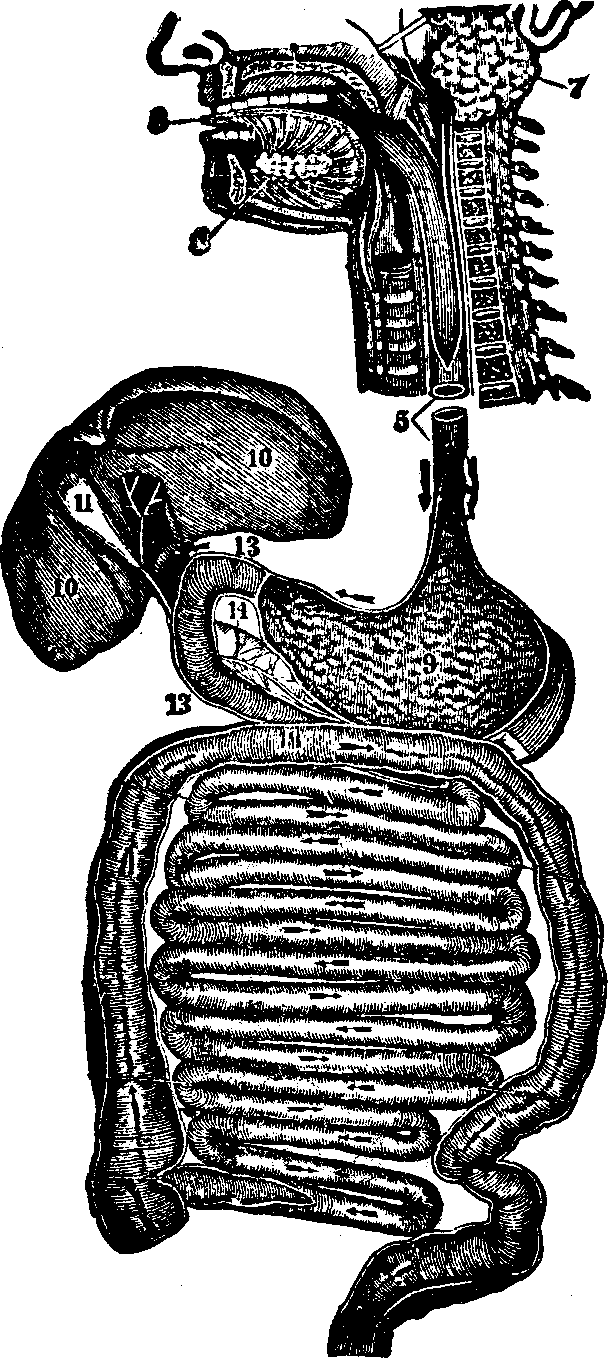

Fig.

34. Digestive organs. 3. The tongue. 7. Parotid gland.

8. Sublingual gland. 5. Esophagus. 9. Stomach.

10. Liver. 11. Gall-bladder, 14. Pancreas. 13,

13. The duodenum. The small and large intestines are represented below

the stomach.